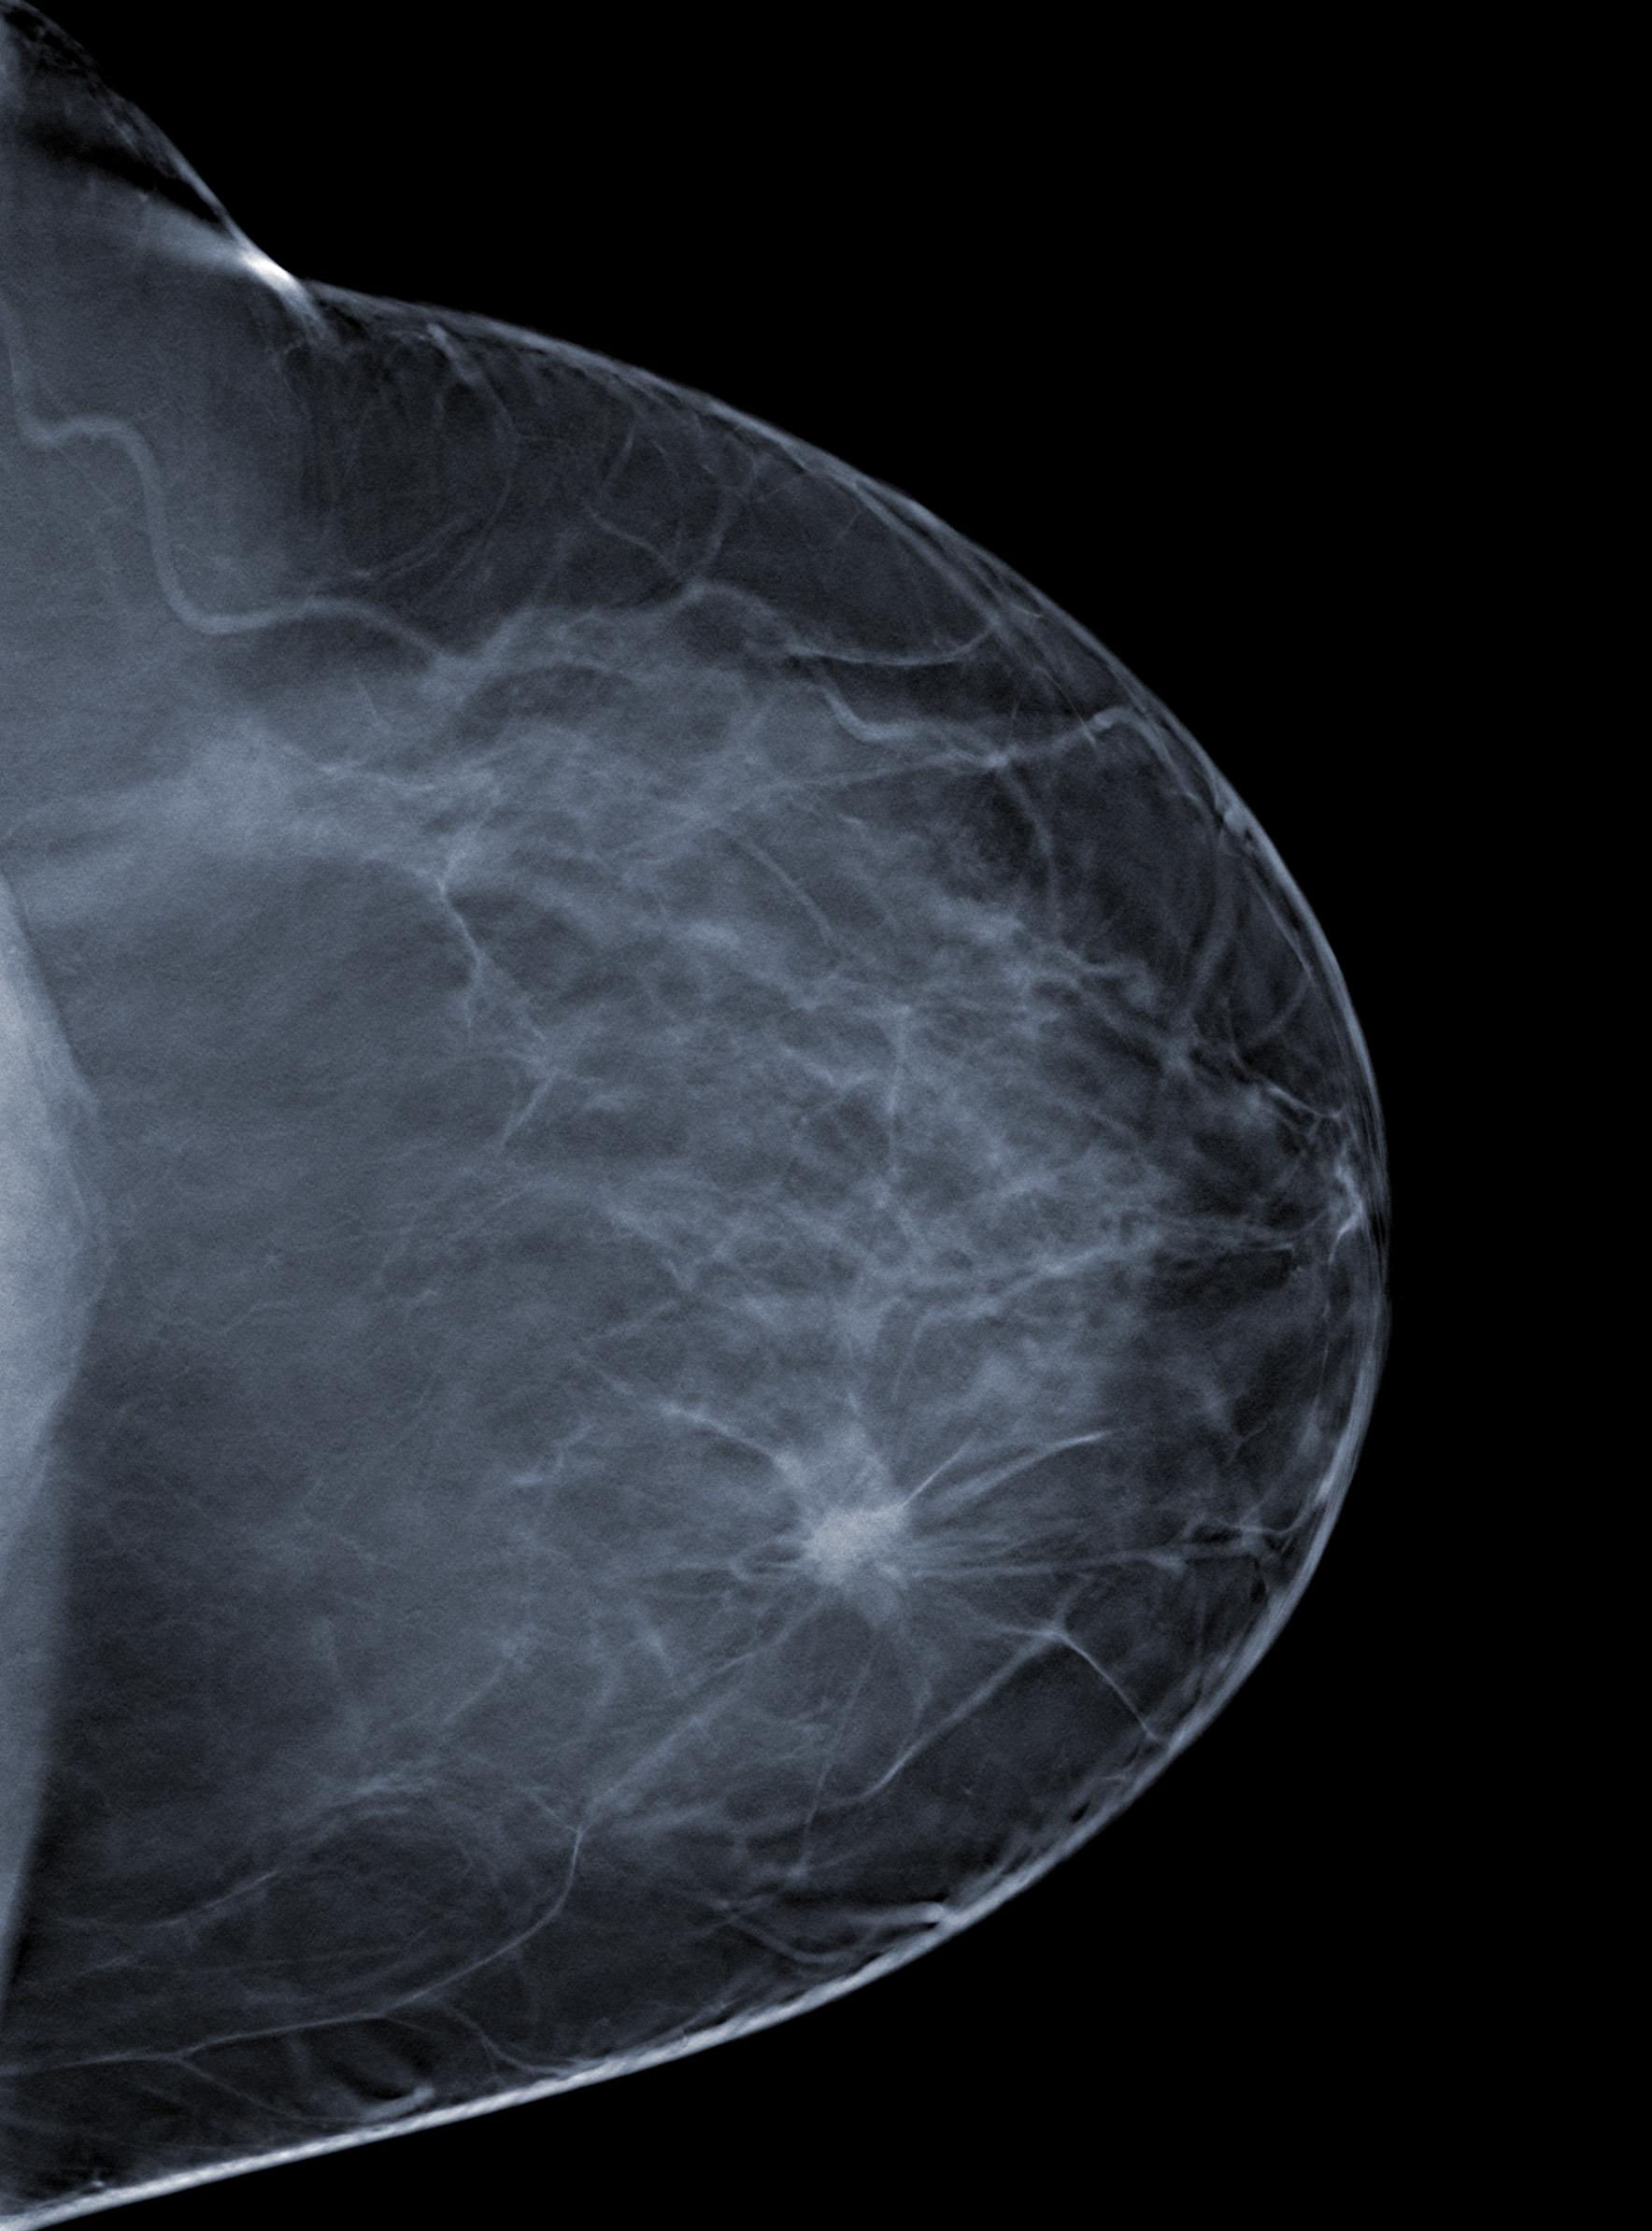

March 31, 2014 — Women whose breast cancer has spread to just a few lymph nodes under their arm are less likely to have their disease recur or to die from it if they have radiotherapy after mastectomy, according to new research to be presented at the European Breast Cancer Conference (EBCC-9) and published in The Lancet. [1]

McGale, Ph.D., a senior statistician in the Early Breast Cancer Trialists' Collaborative Group at the Clinical Trial Service Unit (Oxford, U.K.), analyzed results from 3,786 women in 14 randomized trials starting between 1964-1982, who had been given mastectomies along with the surgical removal of lymph nodes under the arm (axillary dissection) and who were then randomized to receive either radiotherapy to the chest wall and surrounding regions or to no radiotherapy. The women fell into three categories: those with no cancer in the lymph nodes, those with cancer in one, two or three lymph nodes, and those with cancer in four or more lymph nodes. The women were followed up for an average of just over 11 years, and data on the number of recurrences and deaths were available up to 2009.

"In 700 women in whom the pathologists could find no sign that the nodes were affected, radiotherapy did not reduce the risk of recurrence or of dying from breast cancer," said McGale. "However, in the 1,314 women who had between one and three positive nodes, radiotherapy reduced the recurrence rate by nearly a third (32%) and the breast cancer death rate by a fifth (20%). Giving radiotherapy to these women led to nearly 12 fewer recurrences of breast cancer per 100 women after ten years, and eight fewer deaths per 100 women after 20 years."

He found that the percentage reductions in the recurrence and death rates in the 405 women who had only one positive node were similar to those for the women who had two or three positive nodes.

For the 1,772 women with four or more positive nodes, radiotherapy also reduced the recurrence rate (by 21%) and the breast cancer death rate (by 13%). Here, radiotherapy for these women led to nine fewer recurrences of breast cancer after ten years and nine fewer deaths after 20 years per 100 women.